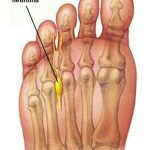

Το Νευρίνωμα Morton περιγράφηκε για πρώτη φορά το 1876 ως περινευρική ίνωση- εκφύλιση του κοινού δακτυλικού νεύρου του άκρου ποδός. Συχνότερα συναντάται στο 3ο μεσοδακτύλιο διάστημα του ποδός. Χαρακτηριστικός είναι ο νευροπαθητικός τύπος του πόνου που οφείλεται σε χρόνιο ερεθισμό του νεύρου. Η πάθηση εμφανίζεται συχνότερα σε γυναίκες ηλικίας από 20- 50 ετών με λεπτά πόδια που φορούν συνήθως στενά και ψηλοτάκουνα υποδήματα.

Οι ασθενείς περιγράφουν αίσθημα καύσου στην πελματιαία επιφάνεια του ποδός στο 3ο συνήθως μεσοδακτύλιο διάστημα, υπαισθησία στα αντίστοιχα δάκτυλα, συμπτώματα που επιδεινώνονται με χρήση στενών υποδημάτων με ψηλό τακούνι.

Η διάγνωση τίθεται από το ιστορικό και την λεπτομερή κλινική εξέταση. Στην διαφορική διάγνωση θα πρέπει ο θεράπων ιατρός να σκεφτεί την μεταταρσαλγία (πτώση των μεταταρσίων), το κάταγμα εκ κοπώσεως του αντίστοιχου μεταταρσίου (stress fracture), την οστεοαρθρίτιδα και την οστεονέκρωση της κεφαλής του μεταταρσίου οστού. Σε ορισμένες περιπτώσεις για την ολοκλήρωση του ελέγχου χρειάζονται περαιτέρω εξετάσεις, όπως ακτινογραφίες ή ακόμα και μαγνητική τομογραφία με ενδοφλέβια έγχυση σκιαγραφικού.

Η θεραπεία μπορεί να είναι συντηρητική ή και χειρουργική. Στη συντηρητική θεραπεία ανήκουν η κρυοθεραπεία, τα υπέρηχα, οι διατατικές ασκήσεις, η χρήση ορθοπαιδικών πάτων ανύψωσης της εγκάρσιας ποδικής καμάρας. Στην τελευταία περίπτωση ο ασθενής πρέπει να υποβληθεί σε πελματογραφία σε εξειδικευμένο κέντρο ώστε να κατασκευαστεί ειδικό πέλμα αποφόρτισης των μεταταρσίων κεφαλών. Σε περίπτωση αποτυχίας των ανωτέρω θεραπευτικών μέτρων, έχει ένδειξη η τοπική έγχυση κορτιζόνης που όμως δρα ανακουφιστικά αφήνοντας τον ασθενή ελεύθερο από τας συμπτώματα για κάποιο χρονικό διάστημα. Εάν ο ασθενής εξακολουθεί να υποφέρει τότε η χειρουργική θεραπεία με την αφαίρεση του νευρώματος Morton δίνει την τελική λύση του προβλήματος.

Νευρίνωμα Morton στο τρίτο μεσοδακτύλιο διάστημα του ποδός που προκαλεί άλγος στην περιοχή και στα αντίστοιχα δάκτυλα.